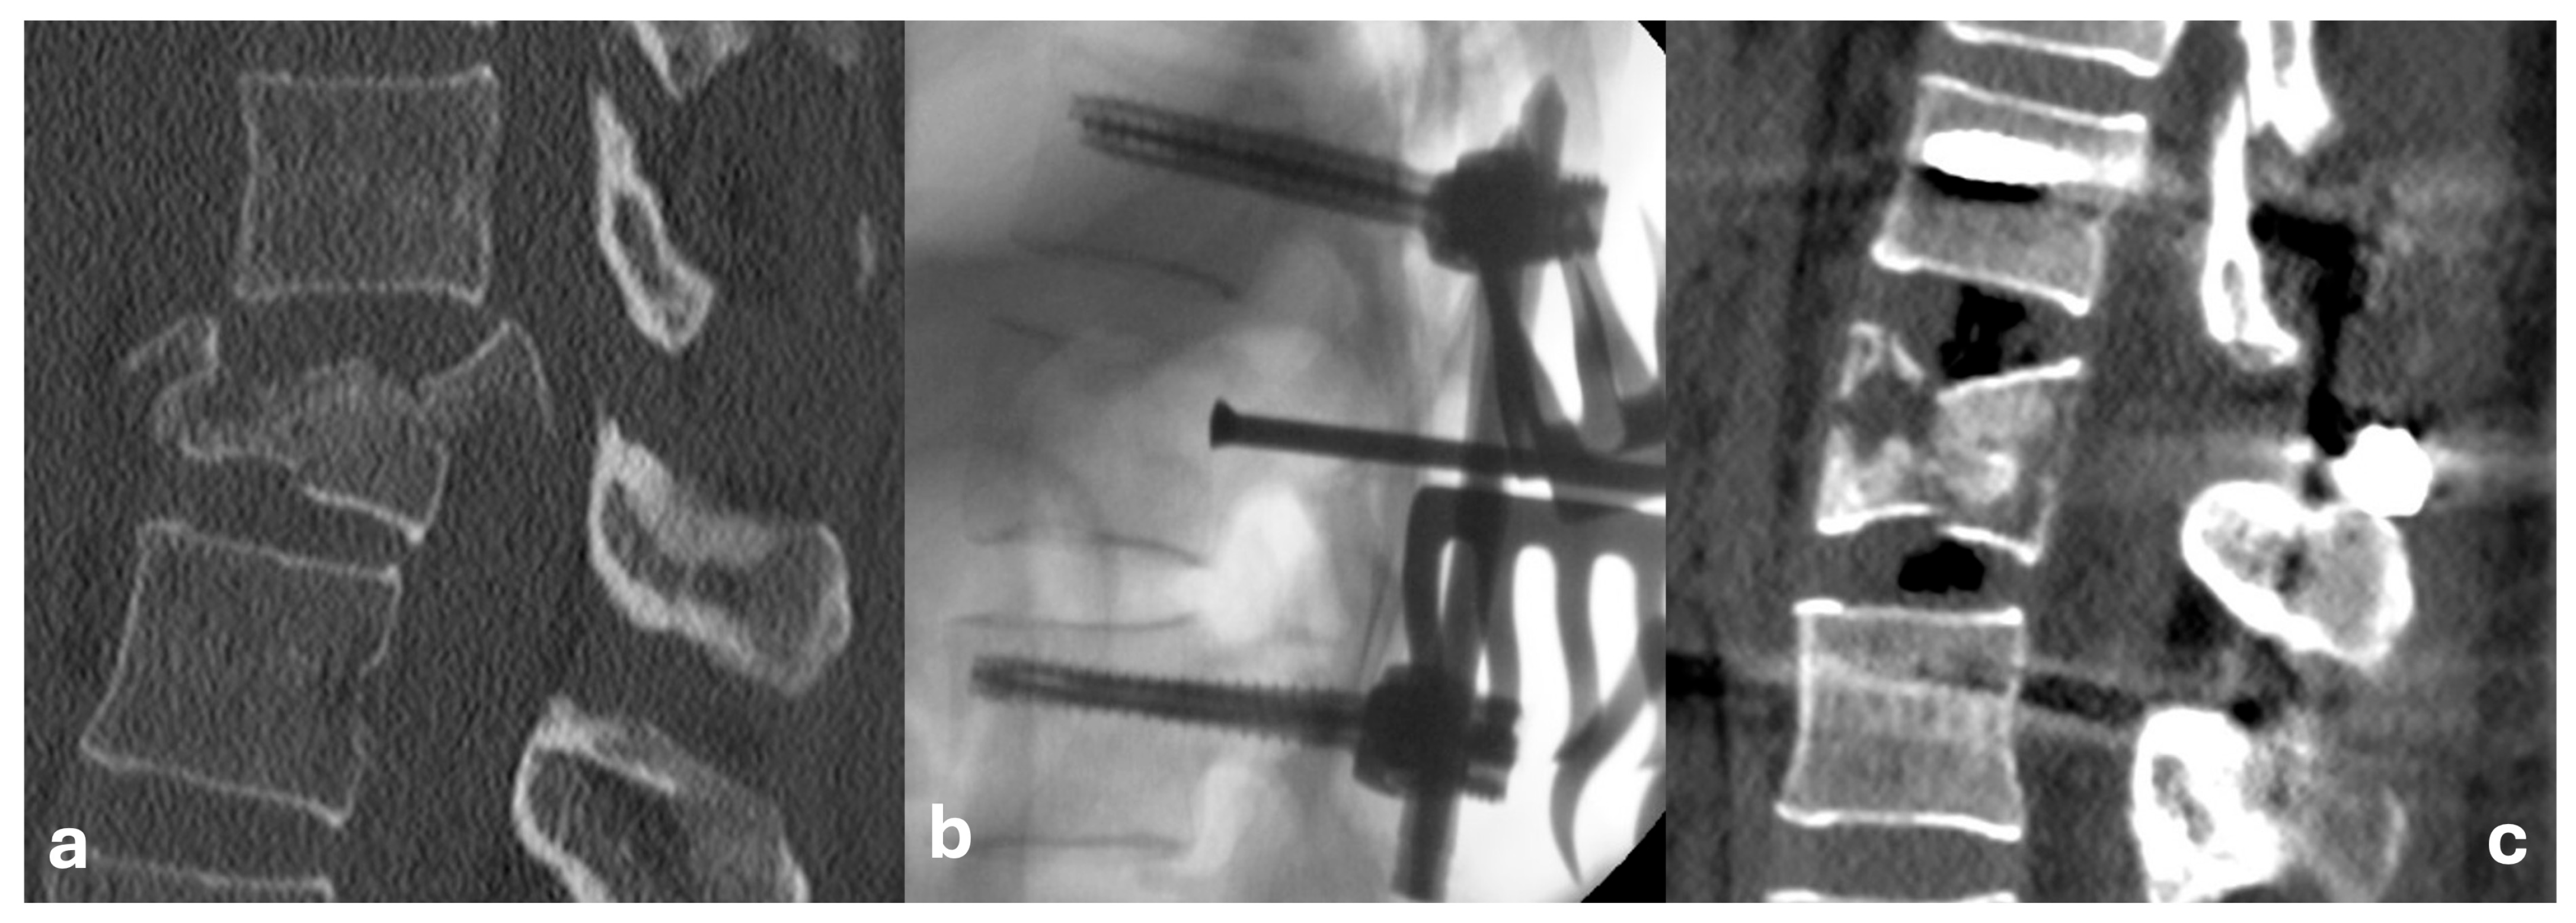

Figure 1. Combined reduction technique: (a) CT sagittal plane projection (bone window) of an L1 AO Type A4 fracture; (b) Perioperative C-arm guided lateral projection radiograph of a direct fracture reduction using an impactor; (c) CT sagittal plane projection showing final lordosis achieved through ligamentotaxis.

The surgical procedure was typically performed within 48 h of trauma for neurologically intact patients, while individuals with neurological deficits underwent surgery in the shortest possible interval, no later than 6 h. The operations were performed in the prone position, through a standard posterior midline approach. Screws were inserted transpedicularly according to Magerl’s technique under radiographic control using a conventional C-arm in two projections. Given the relatively younger cohort of patients and generally good bone quality, a bisegmental instrumentation (2 + 2 screws) was always sufficient. Depending on the individual patient, this procedure was either definitive or, based on the postoperative CT findings, it was decided to perform an additional anterior approach (typically transthoracic partial or complete corpectomy with the placement of an expandable cage, augmented with autologous bone grafts or synthetic bone substitutes). In cases of lower lumbar vertebral injuries (L2 and below), anterior approaches were conducted through lumbotomy. In patients with neurological deficits, decompression was consistently achieved through wide laminectomy. For neurologically intact patients, this procedure was primarily performed when spinal canal stenosis exceeded 50%, as a preventive measure against potential neurological deterioration during postoperative mobilization, and to aid in the direct reduction of the fracture. We performed the direct reduction by “pushing” the dislocated fragments into place at the posterior wall of the injured vertebral body using a dedicated impactor. This technique (alone or in combination) was chosen in cases of spinal canal stenosis estimated at over 50–60%, as assessed by the indicating surgeon, and in all cases of neurological deficits. Indirect reduction was typically performed in patients with segmental deformities, usually with less significant stenosis of the spinal canal (i.e., <50%), and only if there was no necessity for direct exposure of the canal. To achieve indirect reduction, we employed specialized instrumentation to perform ligamentotaxis. This technique involves applying targeted tension to the longitudinal ligaments of the spinal column by applying lever forces to the inserted screws. In certain cases, both direct and indirect reduction techniques were used (Figure 1).